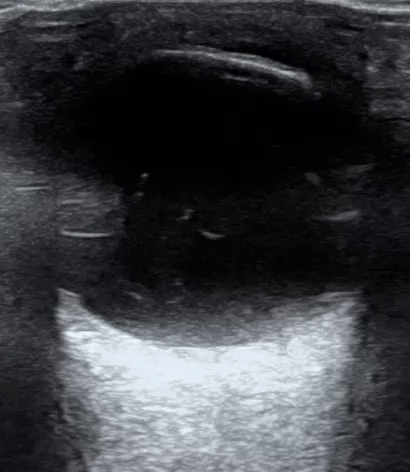

Posterior Vitreous Detachment Ultrasound

Posterior vitreous detachment pvd.

Linear echogenic membrane in the posterior compartment. Ultrasound can easily distinguish vitreous detachment from retinal detachment by looking to see if the detachment is tethered at the optic disc or not. In contrast to rd a pvd takes on a swaying seaweed appearance. The patient was discharged with no specific treatment.

A posterior vitreous detachment is a condition of the eye in which the vitreous membrane separates from the retina. Although less common among people in their 40s or 50s the condition is not rare for those individuals. The sonographic appearance of isolated posterior vitreous detachment includes the following characteristics 3. Diagram of the vitreous cavity during posterior vitreous detachment.

Ophthalmology did see the patient in the ed and agreed that this was a posterior vitreous detachment.